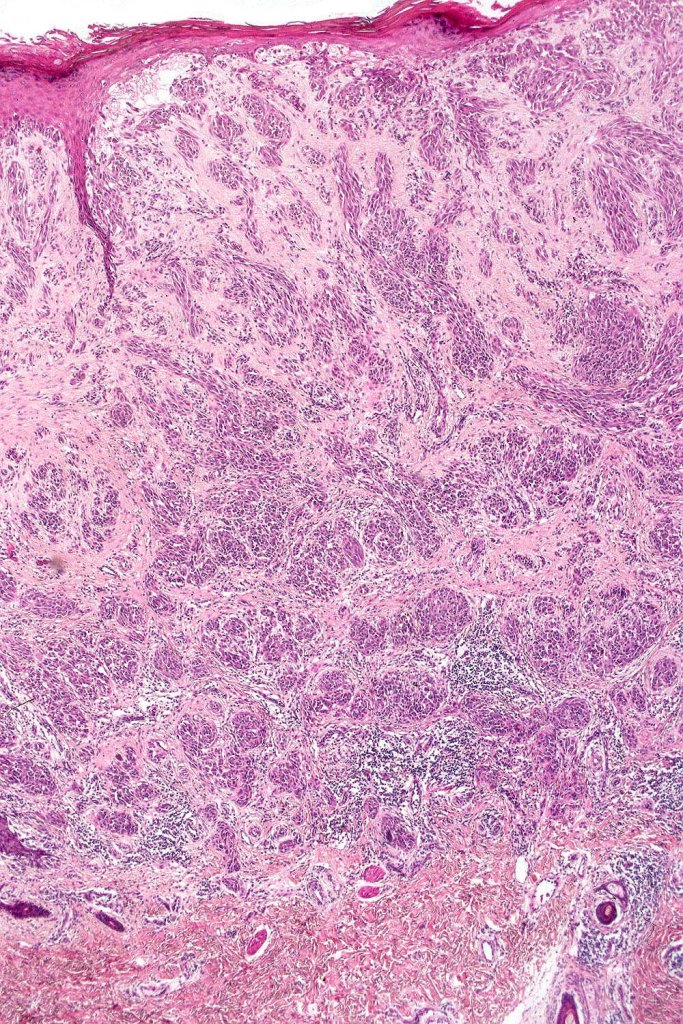

•Hyperkeratosis & acanthosis, sometimes very marked

•Superficial vascular ectasia very frequently present

•Junctional nests often vertically orientated, dyscohesive with a surrounding retraction artifact

•Spindle cell nests often display a “raining down” growth pattern

•Lymphocytic infiltration at the base of the lesion